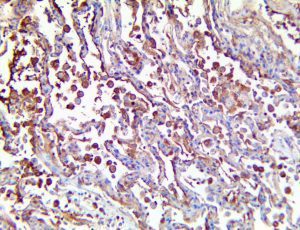

The first cytokines released are interleukin 1β (IL-1β) and tumor necrosis factor-α (TNF-α), which attract a variety of circulating white blood cells (WBCs) to the infection site, including neutrophils, monocytes, macrophages, and natural killer (NK) cells. This response, along with the antipathogenic chemicals released by these cells (i.e., complement), comprise the innate immune response. These cells directly attack the invading pathogen and also release additional cytokines, chief among them interleukin-1 and 6 (IL-6). IL-6 is essential for invoking the adaptive immune response, which calls T-cells, B-cells, and T helper (Th) cells to the infection site. IL-6 also stimulates further recruitment, proliferation and activation of macrophages.

This activation induces inflammatory monocytes to highly express IL-6, starting a localized and then systemic cascade effect that results in hyperproduction of IL-6, which accelerates the inflammatory process. Because IL-6 also increases vascular permeability, excessive levels cause blood vessels to become very leaky. This, along with clotting factors released from vascular endothelial cells, stimulates the coagulation cascade, resulting in microthrombosis (tiny clots), which leads to ischemia and tissue death of the kidney, intestines, heart, liver, brain and extremities.